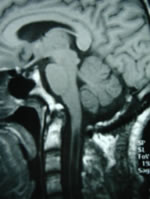

大枕大池的影像表现及鉴别诊断

大枕大池